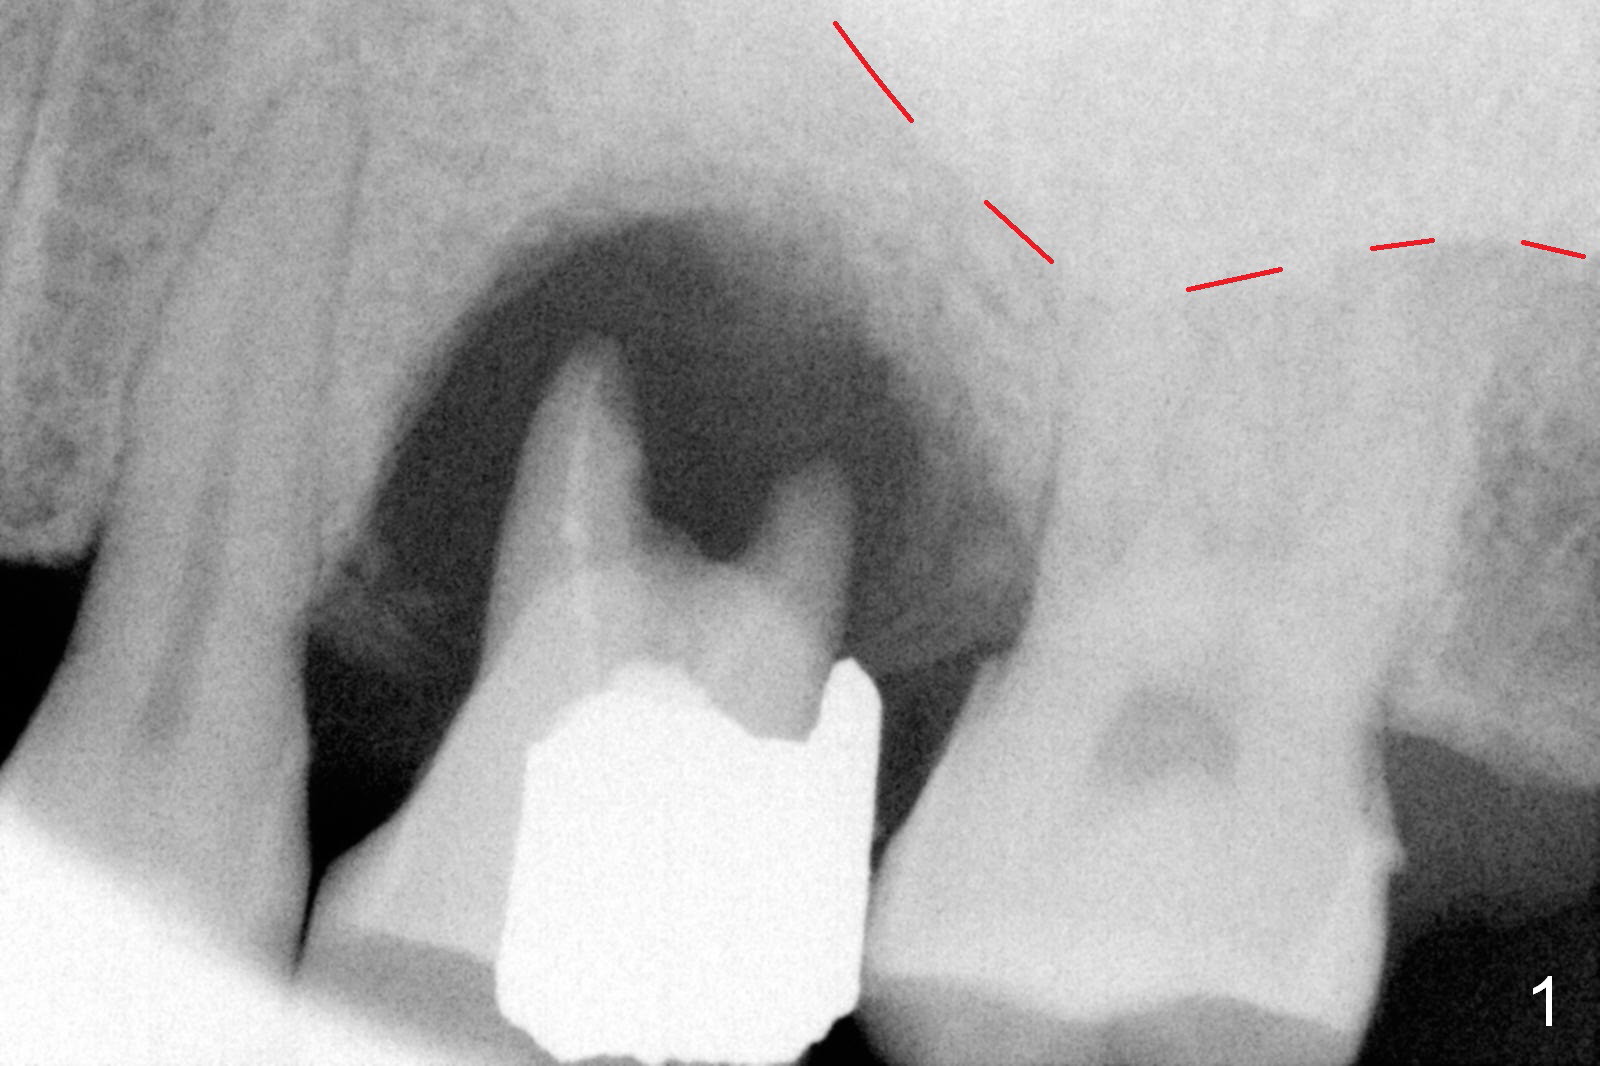

The tooth #14 of a 52-year-old lady had severe bone resorption 6 years ago (Fig.1 (red dashed line: sinus floor)). The bone resorption persists after the tooth exfoliated (Fig.2). Clinically, the buccal plate (Fig.4 (occlusal view) upper panel: B) is concave (take preop photos). #15 scalpel will be used for incision (red line in Fig.4 lower panel, near the lingual plate (L)) and initiation of bone expansion. The latter is followed by bone scalpels, bone blades and RTs at the depth of 14 mm. A 4.5x17 mm Tatum tapered tap is used for 14 mm. PA is taken. If the bone is dense, the depth is less than 14 mm in bone. Use RT2,3 to reach 17 mm. A 5x14 mm bone-level implant is placed (Fig.3). Crown cementation will be done for the tooth #3 before surgery.